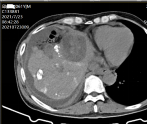

社会快速发展所带来的环境影响,让肿瘤离我们越来越近,当身边的人患有这种疾病时,给患者和亲人带来沉重的思想包袱,而开刀、化疗、放疗等传统治疗方式又给肉体带来更加痛苦的深层次打击。 患者往往对传统治疗望而却步,在绝望中等待生命的终结…… 问 还有希望吗!还有别的治疗方法吗? 答 有!而且还很易于接受。 一根细针,一根细细的PVC导管,或许就能给你带来希望。 通过细针,经皮穿刺病灶,取得细胞学、组织学等资料,可以让我们了解到底是恶性肿瘤还是良性疾病,并知道是什么类型的肿瘤;通过细针,可以让针尖加热,把肿瘤加热失去活性,就像把鸡蛋煮熟了再也孵不出小鸡那样,肿瘤就不再生长,而逐渐吸收变小;通过细针,可以把小小的粒子植入肿瘤,通过粒子缓慢释放能量,把肿瘤灭活,达到治愈肿瘤病灶的目的。 通过导管,进行血管造影进一步确认到底是不是恶性肿瘤;通过导管,并可把载有抗肿瘤药物微球直接注射进入肿瘤血管,缓慢持续长时间杀灭肿瘤细胞;通过导管,可以把给肿瘤供血的血管堵起来,让肿瘤失去血流,失去养料供给,饿死它。 上帝为你关上一扇门的同时,必定会为你打开了另一扇窗,快速发展的社会,科技日新月异,新技术新方法也给肿瘤治疗带来了新的希望。 近年来,淄博市中医医院介入科引入诸多新时代发展带来的前沿新技术,结合数千年古老神秘的中医调理,给诸多患者带来了新的希望和愉快的新生活。 病例一 2015.9 2015.9.11微波消融后 2017.4 肝动脉栓塞并粒子植入,病变直径75mm 2021.4.复查,病变直径35x23mm 病例二 2015.7 肝动脉栓塞并肝癌微波消融 2017.8 MRI复查,病变未见进展 2021.7 CT复查病灶显著缩小 患者后期按时复查,其他处有新增病灶,通过多次介入治疗,至今健在。 介入放射学 是在现代影像学(DSA、CT、超声、磁共振等)方法的引导下,采取经皮穿刺、插管,对患者进行血管造影、采集病理学、生理学、细胞学、生化学检查资料,进行药物灌注、血管栓塞或消融等"非外科手术"方法诊断和治疗多种疾病。 其特点简便、安全、有效、微创、可重复治疗和并发症少,该技术也适合肺癌、肾癌、胰腺癌、甲状腺结节、肺结节等疾病的治疗。 它将不能治疗的疾病变为可治疗、难治性疾病变为容易治疗、复杂治疗疾病变为简单治疗、大创伤治疗变为微创治疗、危险治疗疾病变为安全治疗。目前许多介入方法成为了主要的治疗方法,甚至取代或淘汰了原来的外科手术。 淄博市中医医院介入科 0533-6699127、6699128 官方微信公众号 长按关注 获取更多健康咨询 淄博市中医医院 淄博市中医医院始建于1952年,是鲁中地区最大的一所集医疗、科研、教学、养生保健四位一体的综合性三级甲等中医医院。是山东中医药大学的附属医院、国家住院医师规范化培训基地、山东省中医药预防保健服务中心。设有21个临床科室,9个医技辅助科室,开放床位700张。医院拥有核磁共振、CT等大型诊疗设备300多台件。 预约电话:0533-6699333、6433111 新院区地址:周村区新建东路1166号(碧桂园对面) 。 电话:0533-6699333、6433111 1.乘坐96路公交车到碧桂园站下车 2.乘坐291路公交车到碧桂园站下车 3.乘坐258路公交车到碧桂园站下车 老院区地址:山东省淄博市周村区新建中路75号(乘坐238路、239路、34路、96路公交车均可到达) 和平路院区地址:张店区和平路18号(南西五路与和平路转盘东北角) 电话:0533-2210092 1.乘坐35路、121路、132路、95路公交车和平小区站下车北行100米即到。 2.乘坐138路、223路公交车天星小区站下车东行200米即到。 3.乘坐96路、126路、12路公交车中国陶瓷馆站下车南行600米即到。官方抖音